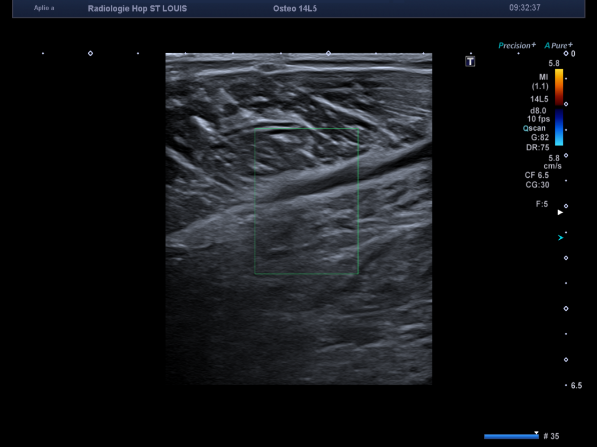

Un contrôle est réalisé chez ce patient une semaine plus tard, devant une persistance de la douleur.

Voici le résumé de l’examen.

Une majoration de l’hématome est alors détectée.

Mais l’échographiste n’arrête pas son regard uniquement sur cet hématome, il vérifie la perméabilité des réseaux veineux superficiel et profond.